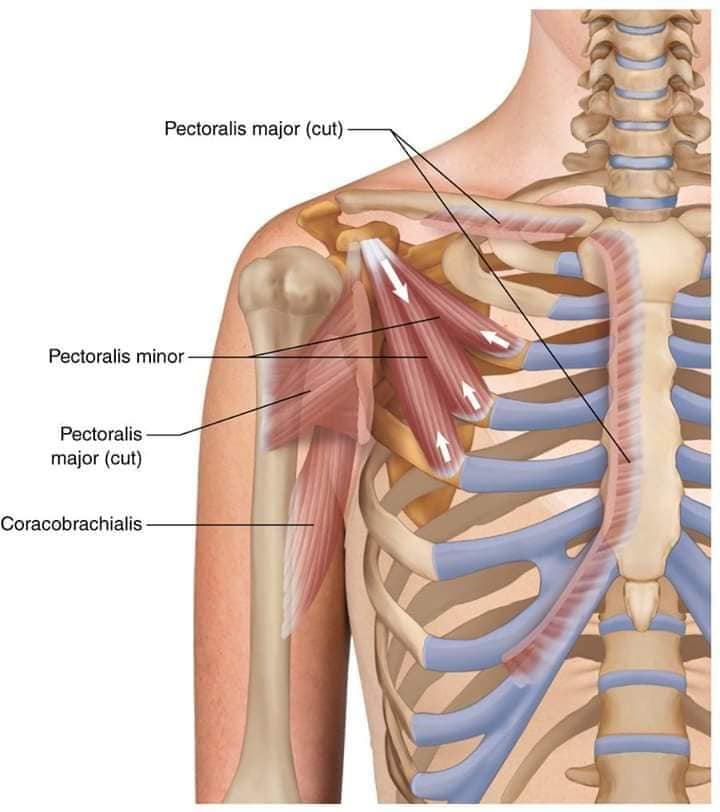

Поверхневі спинні м'язи

М'язи, що піднімають лопатку: Трапецієподібний м'яз: великий м'яз, що покриває верхню частину спини. Його функція - підтримка і рух лопаток, а також забезпечення стабільності хребта.

М'язи, що ведуть лопатку до хребта: Широкий м'яз спини: великий м'яз, що розташований в нижній частині спини. Він відповідає за рухи плечей і лопаток, а також за розширення верхньої частини тулуба.